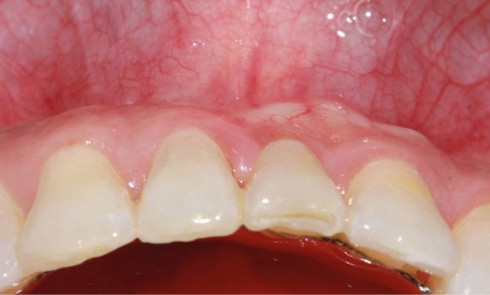

Présentation du cas clinique (fig. 1 à 3) Le patient, âgé de 58 ans, présente un encombrement dentaire mandibulaire de 5 mm dans...